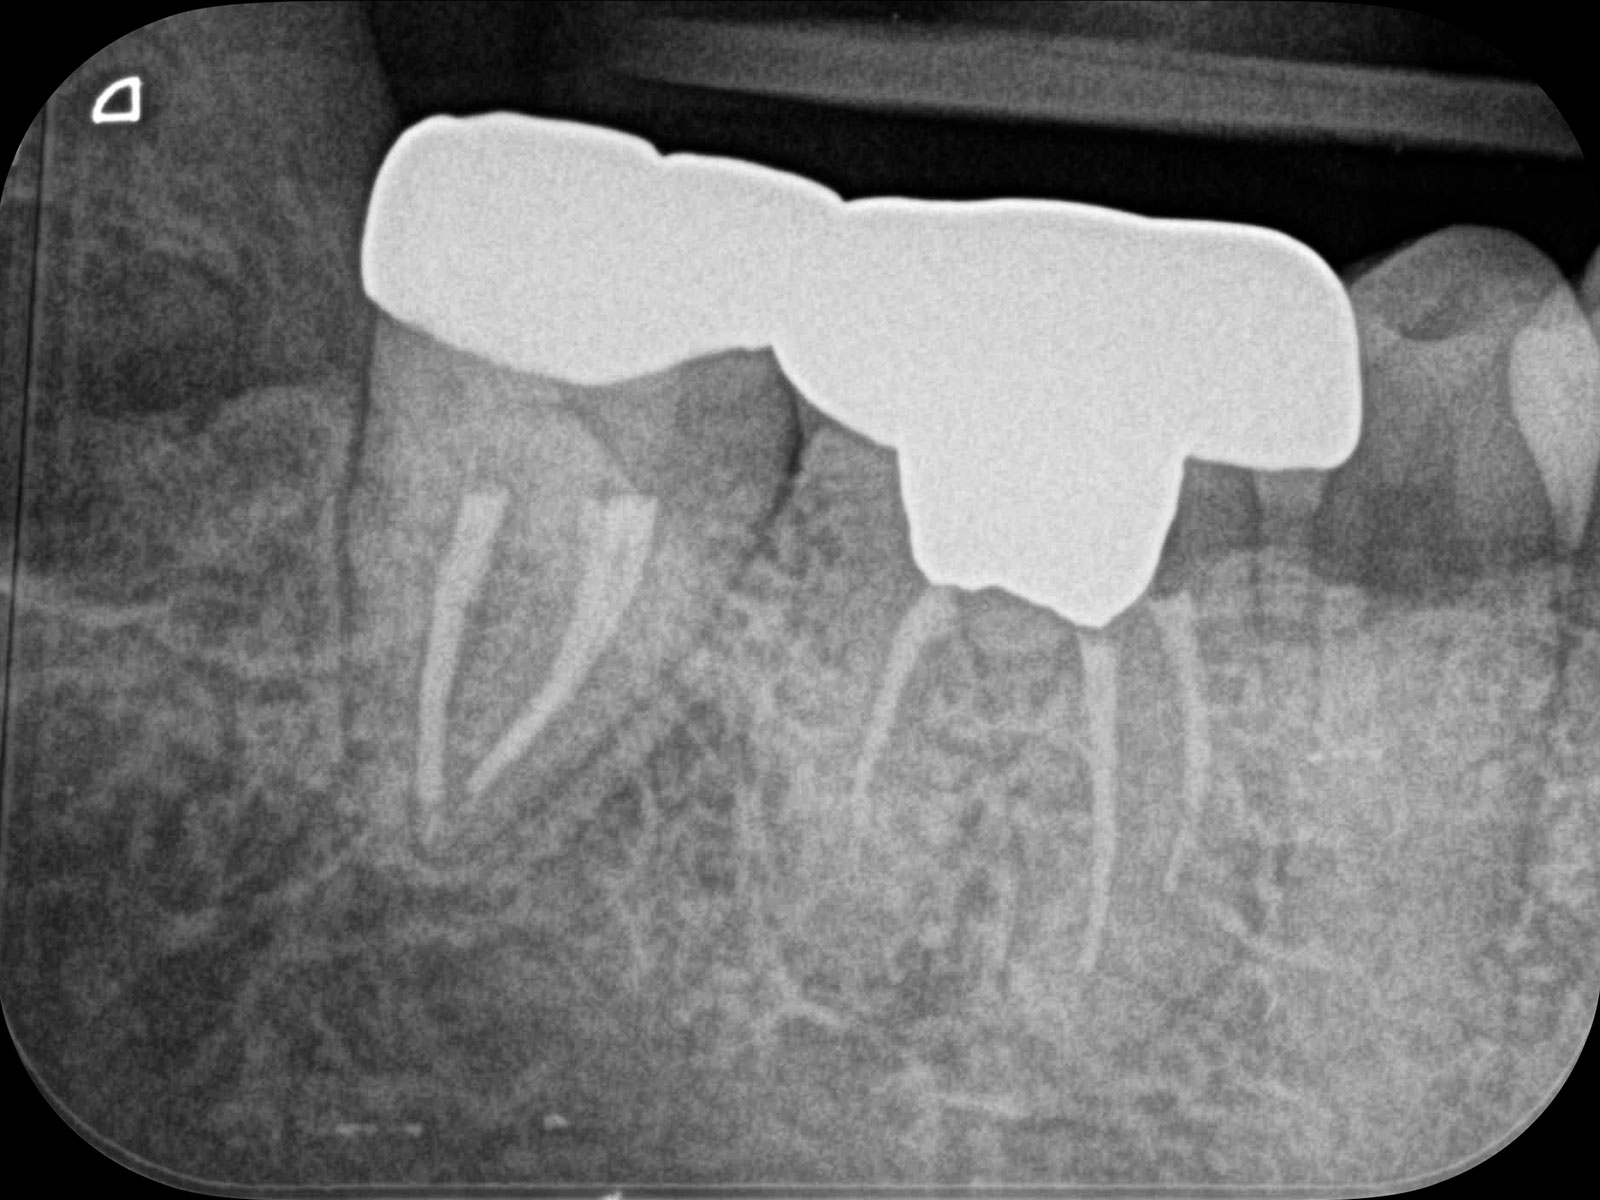

主訴: 噛むと痛い、左で食べれない。他の病院で神経が見つからない。根の先に病気がある。

通常だと手立てがなく、抜歯しかない歯も外科(根尖切除術)で治すことができます。